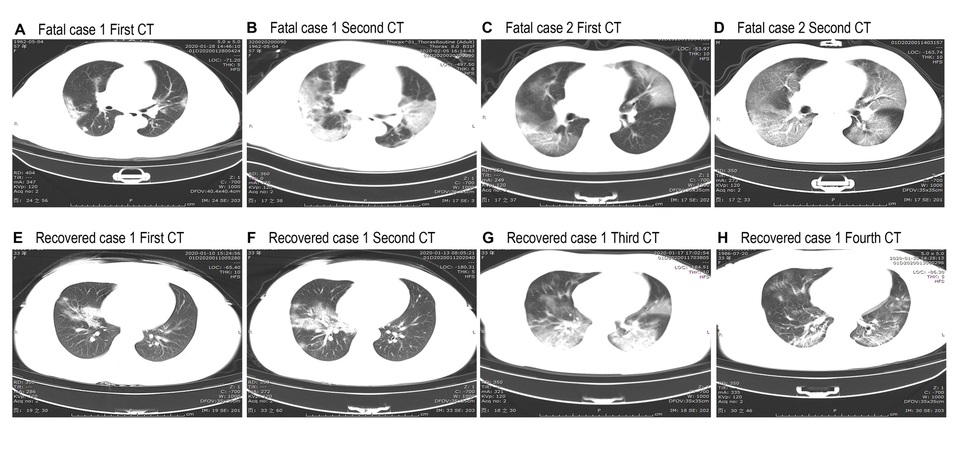

Hình ảnh chup CT ngực ở những bệnh nhân tử vong và bệnh nhân hồi phục do nhiễm Covid-19.